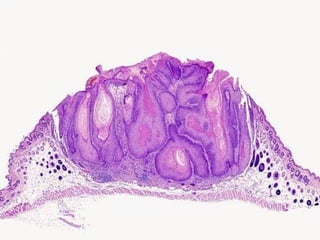

Papillomatosis: Surface elevation caused by hyperplasia and enlargement of

contiguous dermal papillae.

microscopic, papillomatosis

• #43 Keratoacanthoma, the MAIN lesion to differentiate from squamous cell carcinoma

• #44 Keratoacanthoma, the MAIN lesion to differentiate from squamous cell carcinoma

• #45 Keratoacanthoma, the MAIN lesion to differentiate from squamous cell carcinoma